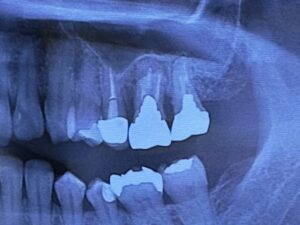

虫歯で奥歯が欠けてズキズキ痛い、噛めない 咬みにくい 食事もだんだんしづらく ついでに歯が冷たい水にしみる!

歯の神経を取る根の治療 根管治療をすれば治ります。治した後は 保険適応でハイブリッドセラミックやCAD/CAM冠インレー クラウンなどで白い歯で治すといいですね。もちろんセラミックやジルコニアの治療もあります。